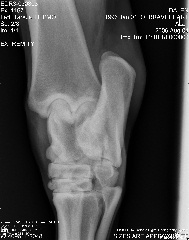

Here are the xrays from today:

Stifle:

stifle

Aileen, carefully reviewing an extensive list of radiographs like you have above for any abnormality even with the original set of full sized radiographs could take up to an hour and an hour more to write about. Reviewing these tiny pictures would be of no value at all. While I don't mind looking at the occasional radiograph the above is beyond the scope of this site.

If you want a second opinion on these I strongly recommend you send them to a certified veterinary radiologist, like you find at a university veterinary school, they could tell you more than I would be able to.

Surgeon says mild to moderate djd in hocks and stifle. His stiffness is much much better, not overall anymore, so I do think the hock injections helped.